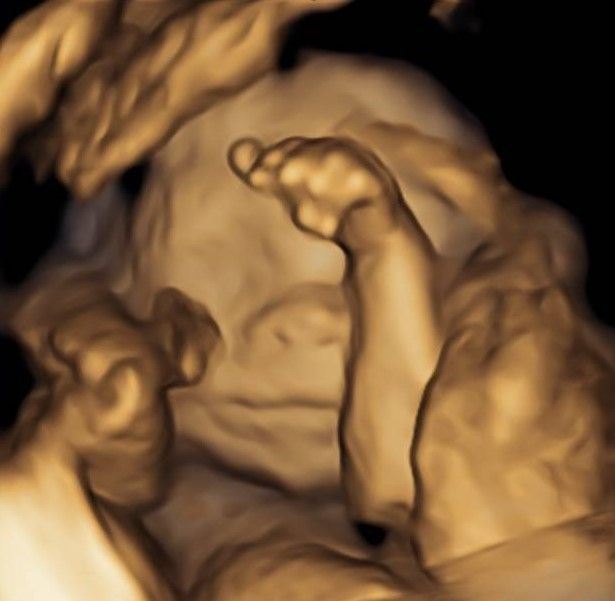

Eseguo in particolare ecografie ostetriche e ginecologiche anche in 3D e 4D per meglio identificare la problematica, offrire diagnosi precise ed un trattamento mirato e personalizzato.

• Arcispedale Santa Maria Nuova - IRCSS Reggio Emilia ecografia ostetrica 3D/4D  •